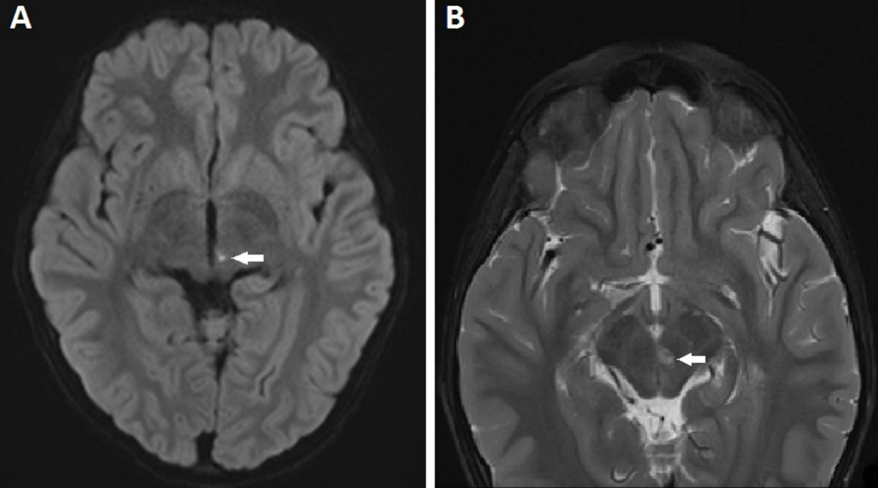

An 8-year-old boy presented to the out-patient department with complaints of sudden-onset binocular vertical diplopia of one day duration. There was no associated significant history except an episode of upper respiratory tract infection one week earlier. General examination demonstrated no abnormalities.The patient’s best-corrected visual acuity was 20/20 in both eyes. Anterior segment examination of both eyes was within normal range, with pupils being round, regular and reactive to light directly and indirectly. Dilated fundus examination was also normal. On motility examination, both eyes showed movement restriction of grade (–4) of upward gaze and (–2) of downward gaze with rotatory nystagmus being present (Figure 1 [Fig. 1]). There were no other neurological abnormalities. Bell’s phenomenon, convergence and horizontal eye movements were completely preserved. An urgent MRI scan of the brain suggested features of localized acute infarct in the left paramedian rostral and dorsal part of the upper midbrain at the level of the red nucleus (Figure 2 [Fig. 2]). Blood investigations revealed hemoglobin 9.9 gm/dl, serum ferritin 6.78 ng/ml, and iron 30 µg/dl with peripheral blood smear showing severe hypochromic microcytic anemia with anisopoikilocytosis being suggestive of IDA. Other blood investigations including random blood sugar, lipid profile, and complete blood cell counts were within normal range. After consultation with a neurologist, a diagnosis of midbrain stroke associated with IDA was made, and the patient was started on cholecalciferol oral drop and sodium feredetate oral syrup. At 2 weeks review, a complete symptomatic as well as clinical improvement was noted (Figure 3 [Fig. 3]).

Figure 2: MRI scan of the brain showing tiny infarct (white arrow) in the left paramedian rostral upper midbrain at the level of the red nucleus; (A) axial diffusion weighted image showing restricted diffusion in the T2 hyperintensity, and (B) axial T2 fat saturated image showing T2 hyperintense focus